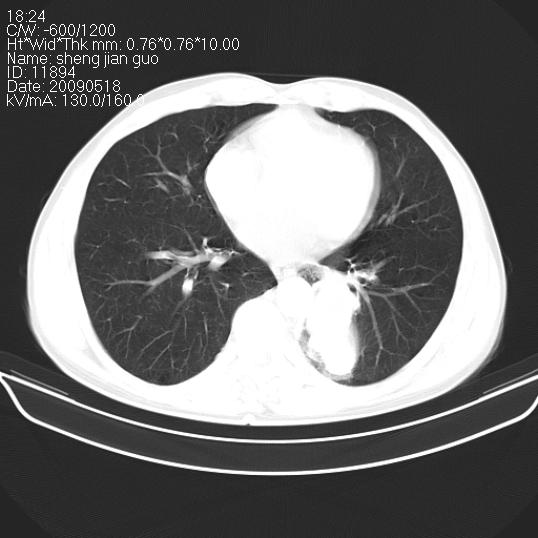

以下是引用zjzjr在2009-5-19 17:25:00的发言:[br]支持楼主考虑,另左肺下叶阻塞性炎症。

以下是引用zhao_bin2008在2009-5-19 17:48:00的发言:[br]支持左肺下叶周围型肺癌并阻塞性肺炎。

以下是引用杀毒软件在2009-5-19 17:36:00的发言:[br]支持楼主

以下是引用zsl6918在2009-5-20 7:10:00的发言:[br]左侧中心型肺癌!